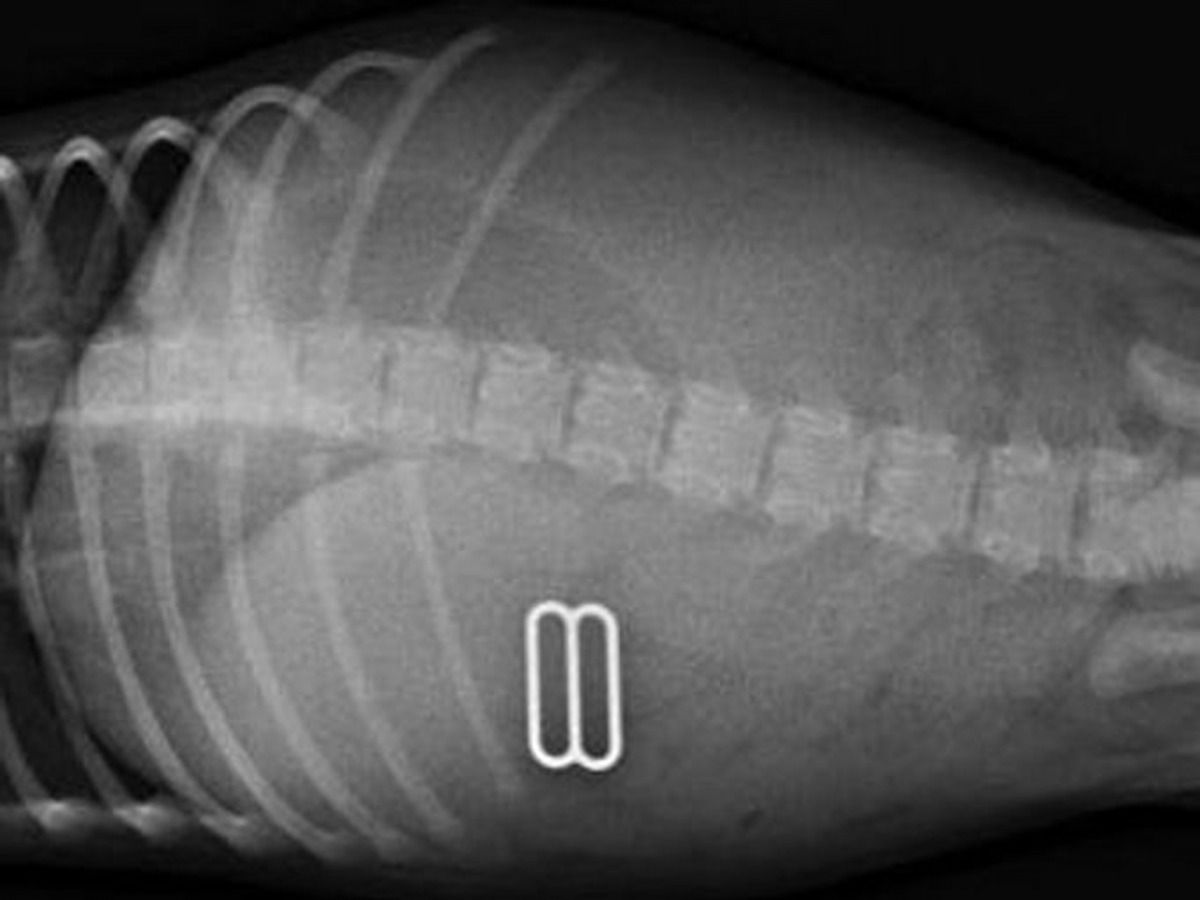

狗狗尤達(Yoda)也不比Marley遜色,牠也成功吞下一個木製「不求人」,更令人驚訝的是,其長度幾乎與牠身軀一樣!還有太多令人驚訝的例子,現在就讓我們一起觀摩一下愛寵們的「創舉」吧!